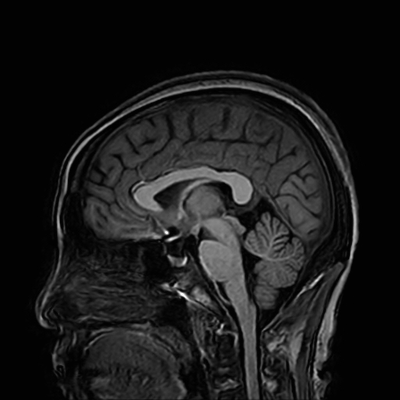

뇌혈관의 구조와 혈액흐름을 촬영하여 뇌혈관질환의 진단과 치료를 위한 중요한 진단 검사입니다.

1. MRA는 자기 공명영상 (MRI) 기술을 이용하여, 혈관에 주입한 조영제가 뇌혈관의 혈류와 상호작용하여 뇌혈관의 세밀한 형태와 혈류를 파악하는 방법입니다.

2. MRA 검사는 뇌의 동맥, 정맥 및 혈관 병태를 진단하고 감시하는 데 사용됩니다. 이 검사는 뇌졸중, 협심증, 혈전 및 혈관 손상 등 뇌혈관질환의 원인을 파악하는 데 매우 유용합니다. 또한, 혈관압이 증가하는 증상이나 뇌출혈, 뇌혈관 기형, 혈관성 뇌종양 등도 진단할 수 있습니다.